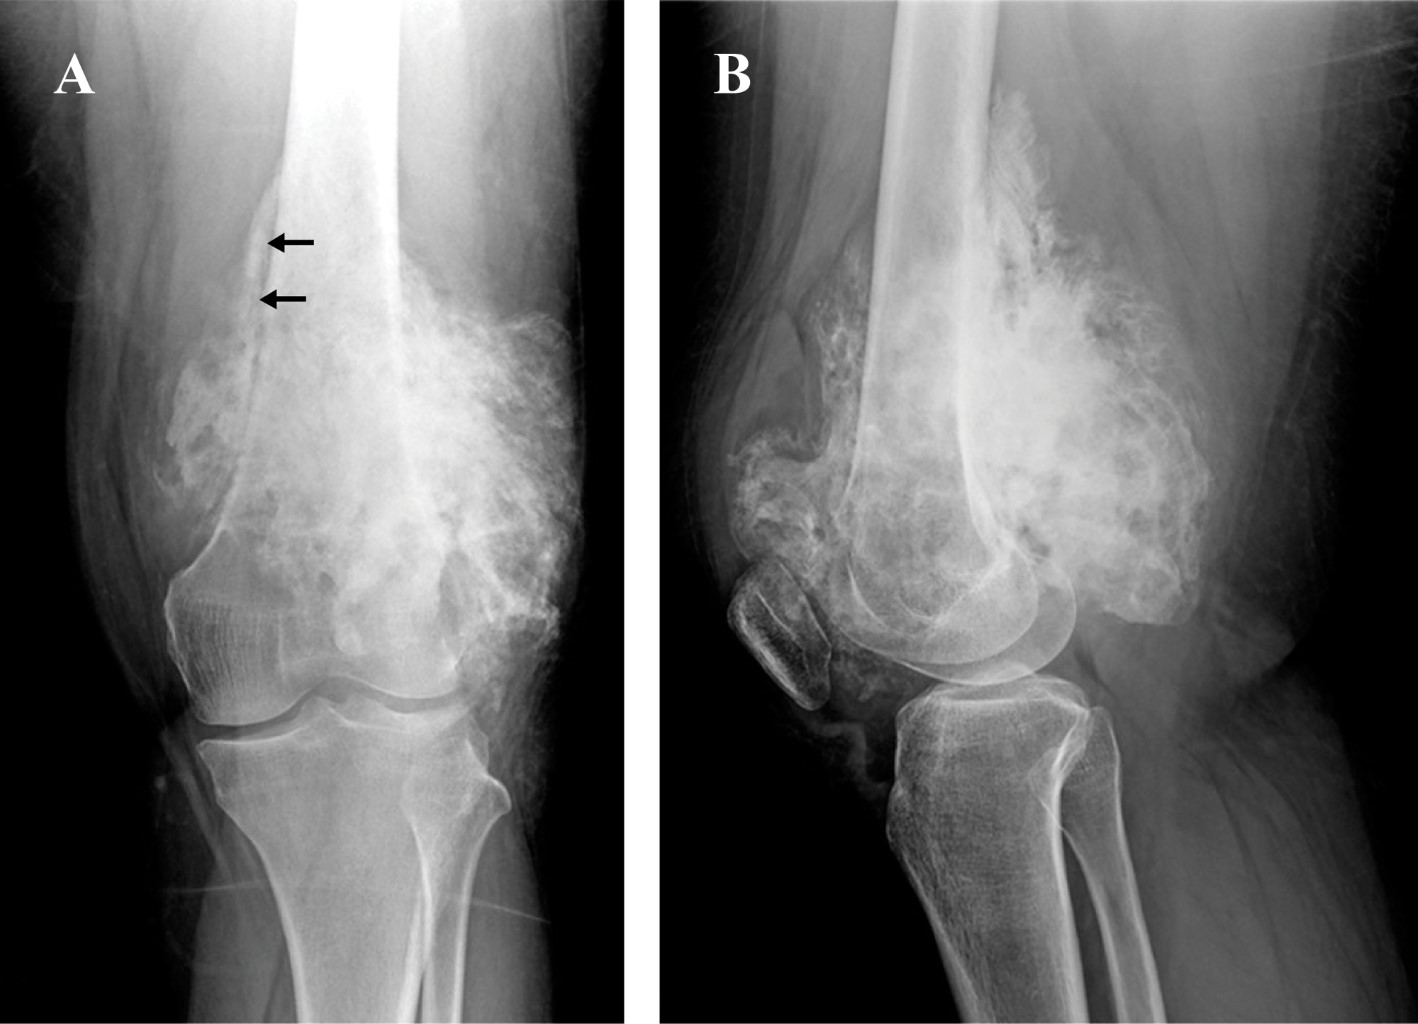

Introducción: el osteosarcoma parosteal convencional es un tumor óseo maligno poco común, que comprende el 4% de todos los osteosarcomas. Aunque es poco común, el osteosarcoma parosteal es el tipo más común de osteosarcoma de la superficie ósea. Presentamos las características clínicas, histológicas y de imagen de una variante histológica rara de un osteosarcoma parosteal, revisamos la literatura y enfatizamos la importancia de la correlación radio-patológica, así como la interpretación de una biopsia representativa para obtener el diagnóstico correcto. Reporte de caso: mujer de 36 años inició su cuadro un año antes de su ingreso al hospital con aumento de volumen en rodilla izquierda y dolor. Los estudios de imagen mostraron una tumoración heterogénea yuxtacortical localizada en la superficie posterior de la metáfisis femoral distal. Se realizó biopsia incisional, con diagnóstico de osteosarcoma parosteal y se realizó resección quirúrgica amplia. De acuerdo con los hallazgos de la pieza quirúrgica se realizó el diagnóstico de osteosarcoma parosteal con componentes de condrosarcoma y liposarcoma de bajo grado. El conocimiento de esta rara variante de osteosarcoma parosteal puede llevar a los ortopedistas oncólogos a considerar otros componentes y proporcionar márgenes quirúrgicos adecuados. Conclusión: presentamos las características clínicas, histológicas y de imagen de un osteosarcoma parosteal con componentes de liposarcoma y condrosarcoma de bajo grado.

Figura 4